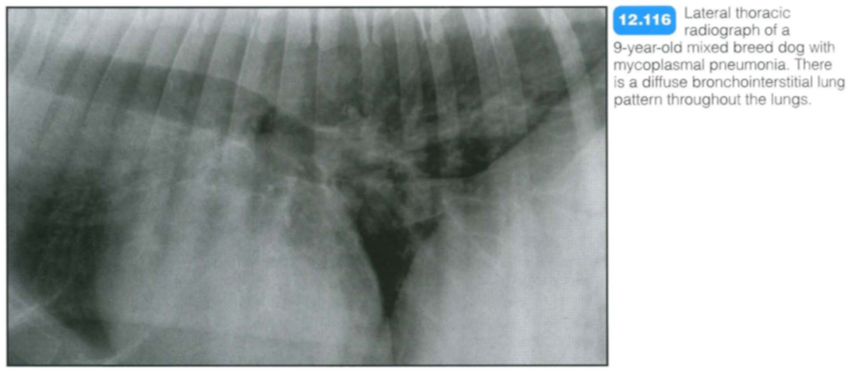

Mycoplasmal pnuemonia

Mycoplasmal pneumonia:

Mycoplasma spp . are small bacteria that are part of the normal oral flora in dogs and cats. In the lungs, mycoplasmal bacteria are involved in lower airway and lung disease, along with other bacteria. Immunodeficient or otherwise compromised animals are predisposed to mycoplasmal disease .

Radiography: